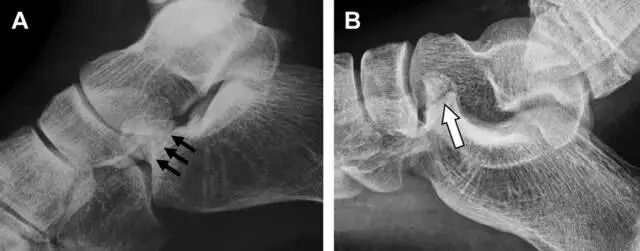

19距骨后突骨折

距骨后突有内侧结节和外侧结节,距骨后突内侧结节撕脱性骨折常发生在背屈内旋的暴力作用下。严重跖屈时,胫骨后缘和跟骨挤压距骨后突外侧结节呈楔形,易发生粉碎性骨折。这些骨折细微且需与三角骨鉴别。侧位片观察距骨后突骨折最佳,常规拍片很难发现,当高度怀疑这种骨折又没法做 CT 时,建议加做多个角度的外旋斜位片(图 5)。

图 5 距骨后突骨折。侧位片(A)和 MRI 矢状位 T1 加权像(B)均示后外侧突的简单骨折(箭头),再次阅片时才发现 X 线片上的骨折;侧位片(C)和 CT 横断面图像示后内侧突的粉碎型骨折(箭头)